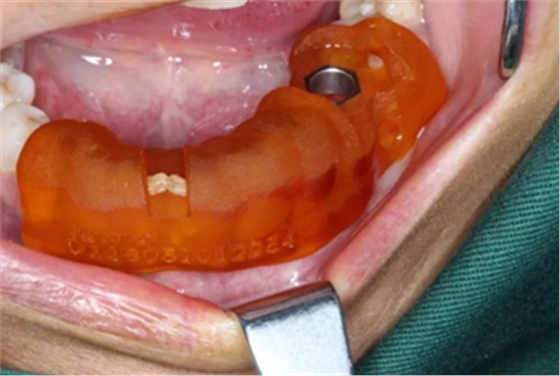

1.碘伏浸泡消毒后的导板在患者口内试戴,就位准确、十分稳固。

根据上述植入和修复方案,立体设计Implant Guide™全程导板,鉴于下颌需避让下颌神经管,并考虑到种植体与颊舌侧、近远中侧的关系,设计在该牙位植入1颗Alpha-Bio Tec ICE 4.2x 10mm的植体。